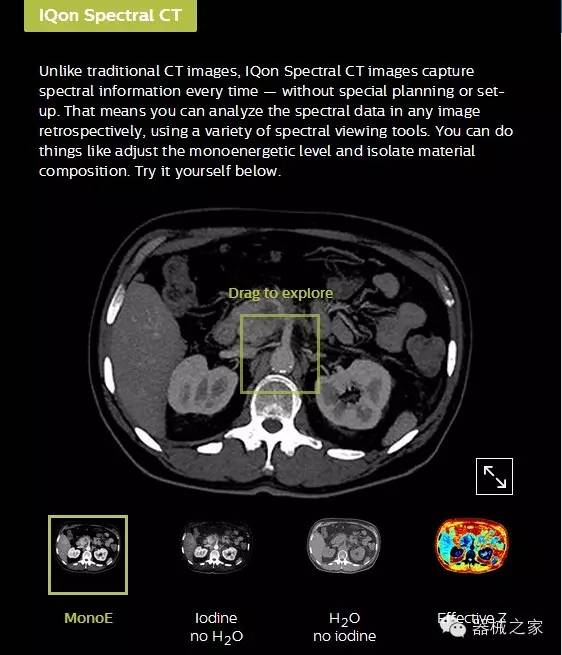

IQon光譜CT能夠按照需求提供光譜量化和工具,并能通過簡單工作流程、在低劑量下對結(jié)構(gòu)進(jìn)行定性分析

IQon光譜CT -- 是業(yè)界首臺以探測器為成像基礎(chǔ)的光譜CT,它可以在單次常規(guī)掃描下獲得傳統(tǒng)解剖影像及光譜功能影像。不僅可以提供精準(zhǔn)的診斷信息,還可簡化工作流程、在低劑量下完成定量與定性分析。